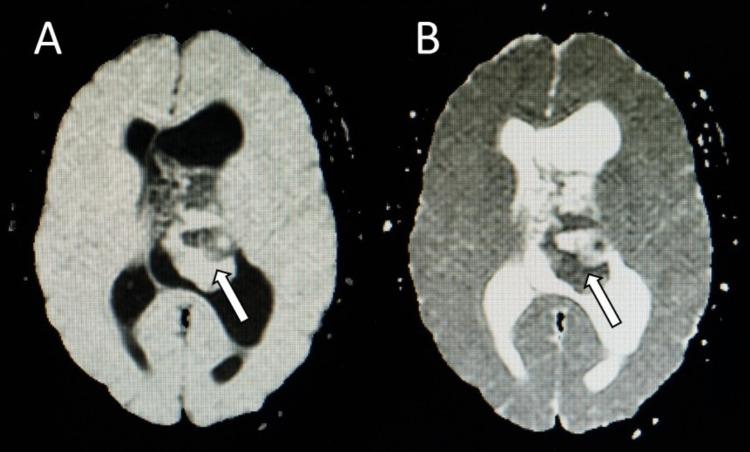

Central neurocytoma (CN) is a rare intraventricular tumor. The common presenting symptoms of CN are headache, vomiting, and visual disturbance, which results from increased intracranial pressure. This report presents a case of CN with unusual clinical presentations. A 25-year-old female with CN presented with a one-day history of unilateral headache, ipsilateral periorbital pain, multifocal paresthesias, and vomiting. Magnetic resonance images showed an intraventricular mass with a soap-bubble appearance and numerous cystic areas typical for CN, causing obstructive hydrocephalus and a midline shift. After one night of rest, her headache, periorbital pain, and paresthesias disappeared. It is possible that the tumor could be mobile with regard to the patient's head position, causing occasional obstruction of the foramen of Monro. Due to the tumor size, which was larger than 4 centimeters, the surgical approach with either gross tumor resection or subtotal resection plus adjuvant radiotherapy should be carefully considered.

中枢神经细胞瘤(CN)是一种罕见的脑室内肿瘤。CN的常见症状为头痛、呕吐和视觉障碍,这些症状由颅内压升高引起。本报告介绍了一例具有不寻常临床表现的CN病例。一名患有CN的25岁女性,有一天的单侧头痛、同侧眶周疼痛、多灶性感觉异常和呕吐病史。磁共振成像显示脑室内有一个呈肥皂泡样外观且有许多典型CN囊性区域的肿块,导致梗阻性脑积水和中线移位。经过一晚休息后,她的头痛、眶周疼痛和感觉异常消失了。肿瘤可能会随着患者头部位置移动,偶尔阻塞Monro孔。鉴于肿瘤大小超过4厘米,应仔细考虑采用肿瘤全切或次全切除加辅助放疗的手术方法。